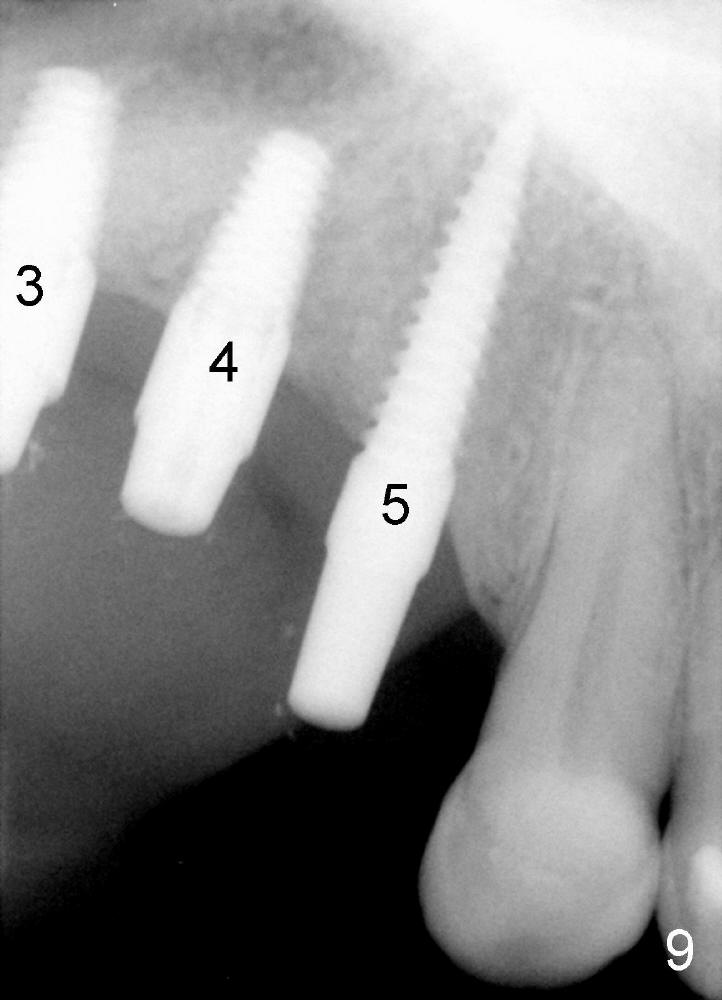

A 3.5x17 mm one-piece implant is placed at #5 and a 4x11 mm two-piece at #4 with crack line buccally (Fig.3 <), while a 4.5x11 mm tap is in place at #3.

Fig.4 shows 4 implants in place with implant apex sticking into the sinus (>, which will be covered by bone graft). Fig.5 is a PA taken post bone graft, while Fig.6 is a section of panoramic X-ray showing the boundary of bone graft (arrowheads) after cementation of a provisional bridge. The latter satisfies the patient's request for cosmetics.